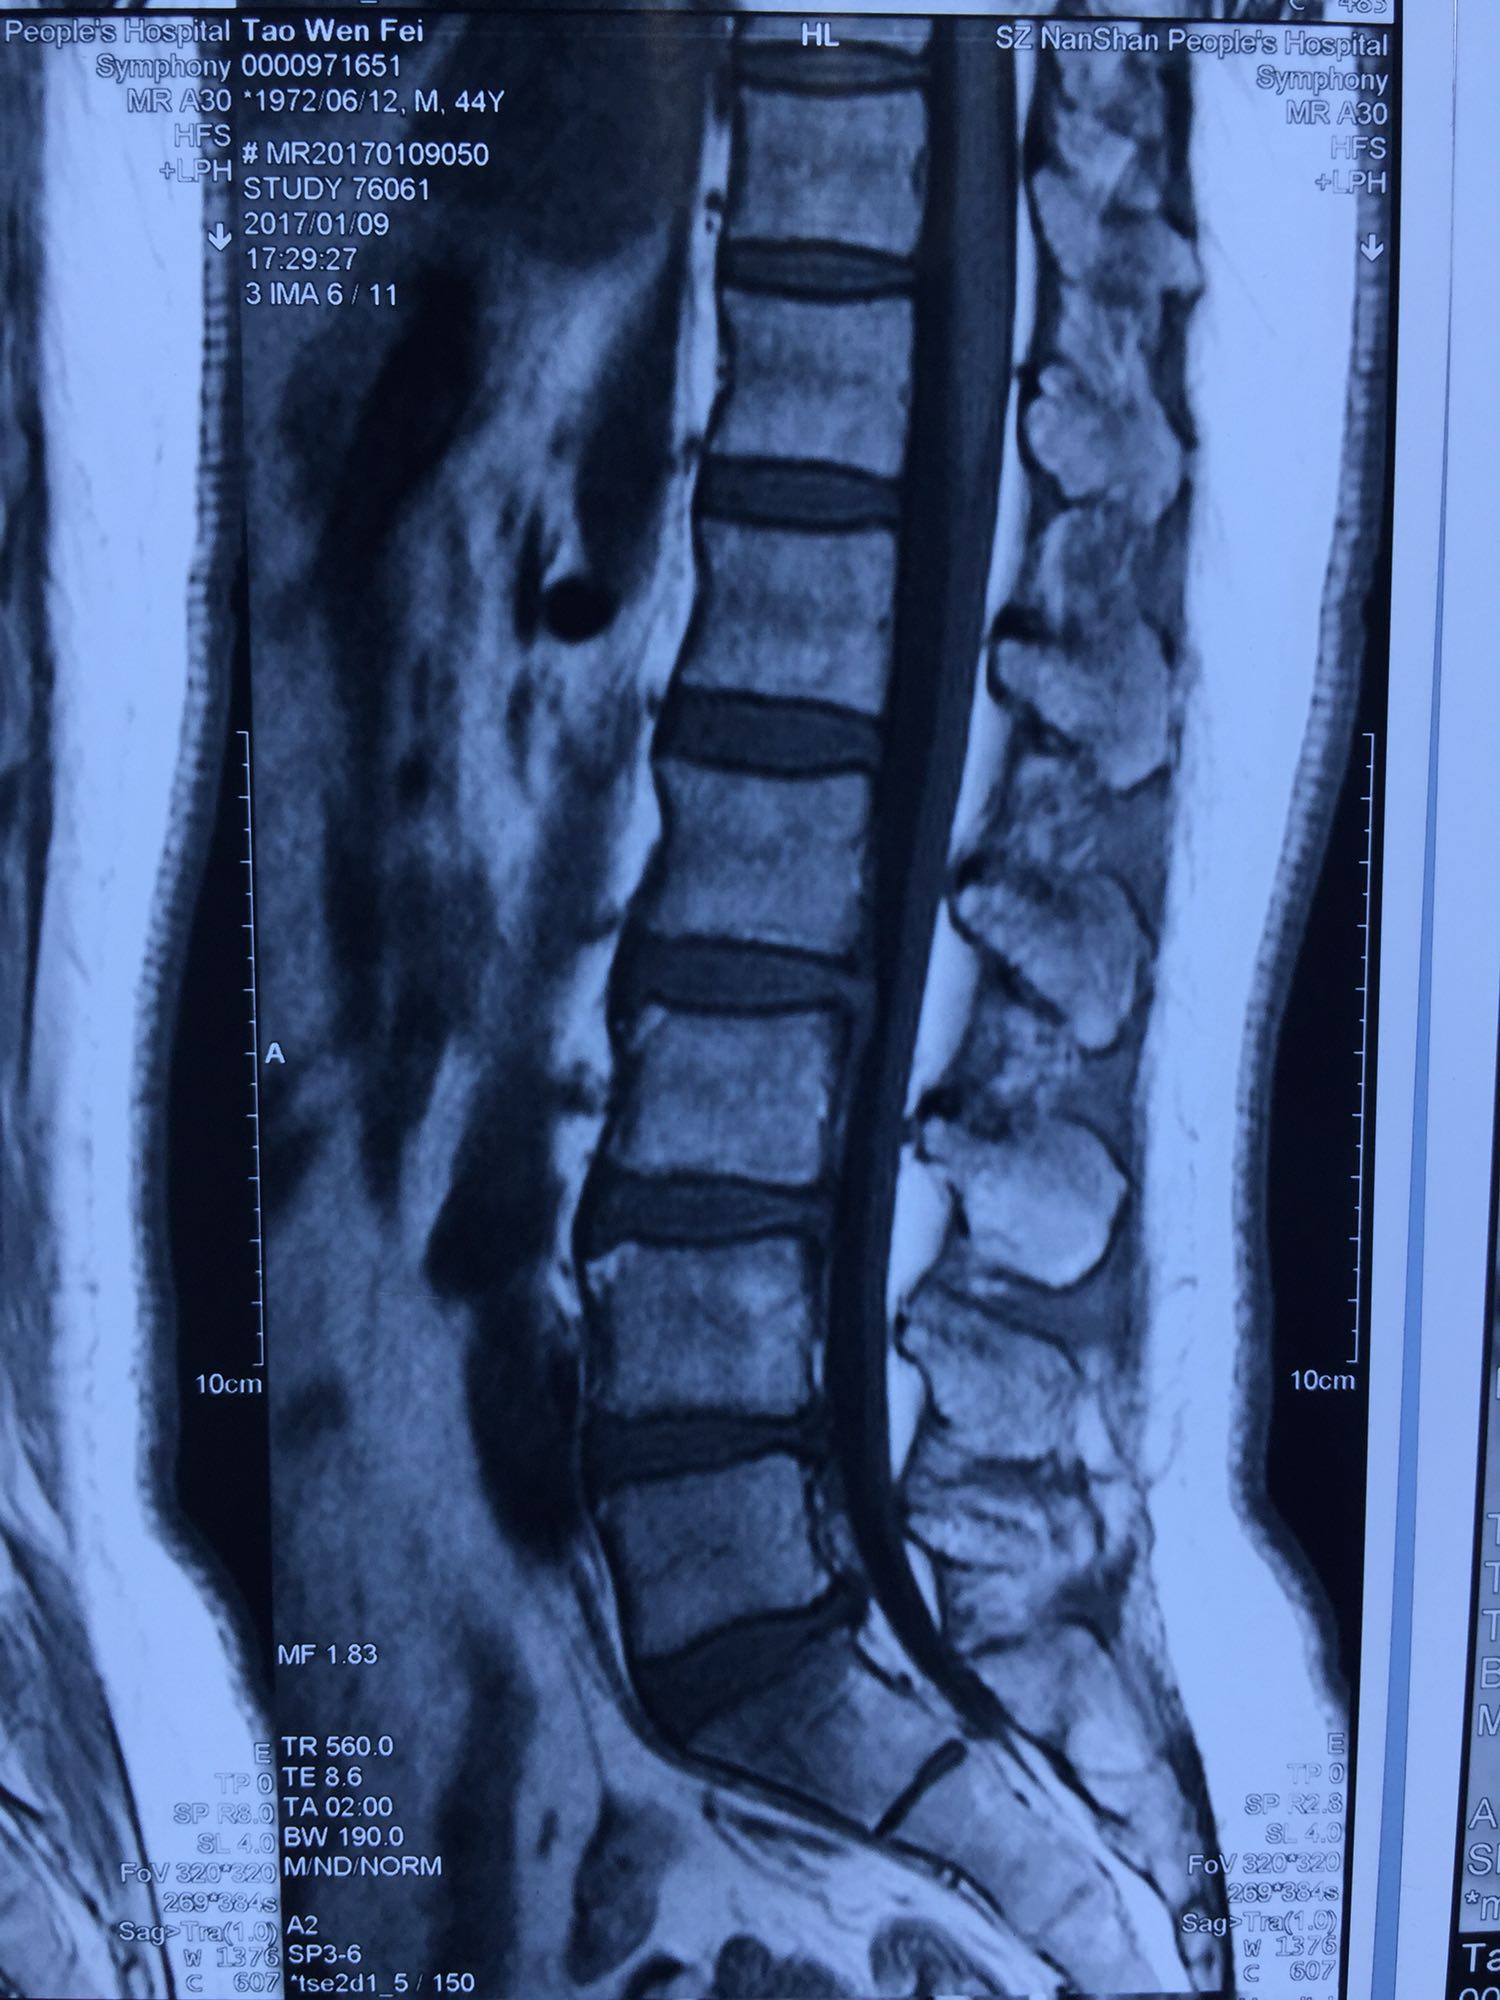

查体:腰23、腰4~骶1椎间有压痛及叩击痛,腰4~骶1右侧有压痛及轻度放散痛。双下肢皮肤感觉正常,肌力肌张力正常,右侧直腿抬高试验阳性(30度),双下肢病理反射阴性。影像学资料如下:

1.腰椎间盘多发性退行性病变; 2.腰椎间盘突出症(多发性) 治疗方案:XLIF+TLIF+后路钉棒系统内固定术

腰23腰34侧方XLIF术+腰45腰5骶1TLIF术+后路腰2~骶1后路钉棒系统内固定术。